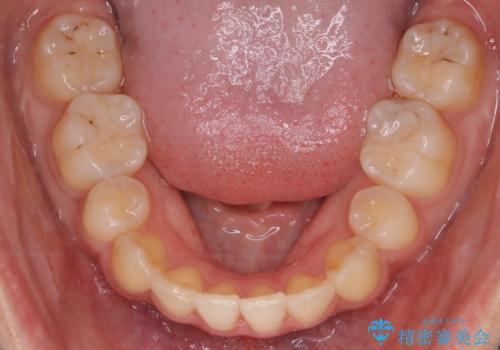

【クリア装置】八重歯の矯正治療

- 八重歯を主訴に来院されました。4番の歯を4本抜歯し、八重歯を並べる計画をたてました。

抜歯をし、スペースを確保したことにより八重歯をきれいに並べることが出来ました。